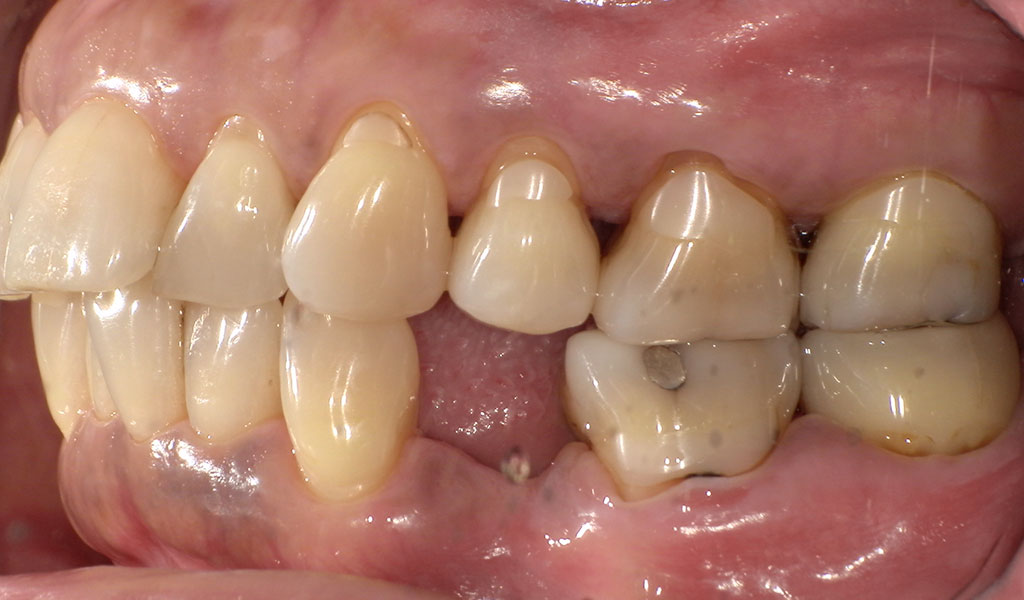

After1(右下4番)

After2(左下4番)